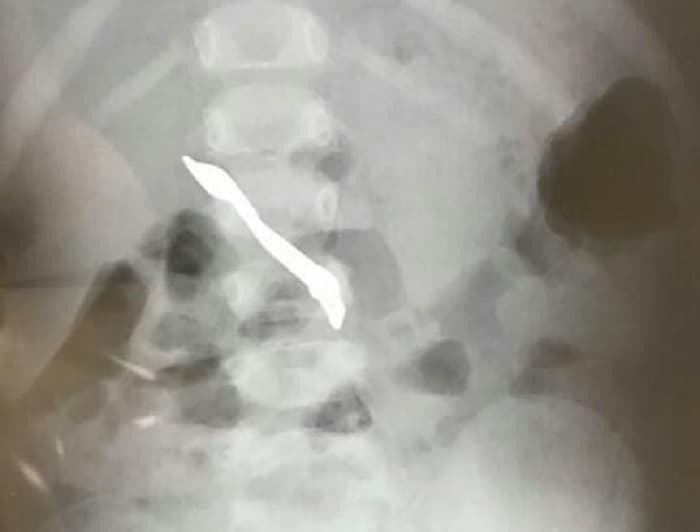

Lea también: Pronóstico reservado para la beba que “resucitó” en Minga Guazú: respira por sí sola pero su estado es críticoLa pequeña paciente está conectada a un respirador, en estado delicado y con pronóstico reservado, aunque la consideran estable por el momento. Se le realizaron dos transfusiones, una de ellas de plaquetas, y se encuentra con sedación intermitente con morfina.

Sin embargo, horas después, durante el velorio, los familiares notaron cambios en la coloración de la piel de la bebé y la trasladaron de urgencia al hospital, donde se comprobó que tenía latidos y se la pasó a una incubadora. Aunque al principio se habló de catalepsia, posteriormente se determinó que se trató de un caso de muerte aparente o Evento Breve Resuelto de Causas Inexplicables (Brue).